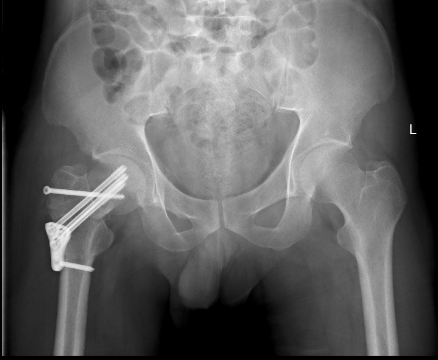

术后2周

在医生为病人解除病痛,救死扶伤的背后,是技术创新、工具升级所提供的推动力。3D打印技术近年来在国内医疗领域探索应用前景被普遍看好,特别是骨科专业。我院骨科走进医疗领域前列,2015年12月首次在骨科手术中使用3D打印技术指导股骨颈骨折切开复位内固定术,为骨科3D技术打开了新局面。随后对创伤骨科及关节骨科中复杂的骨折均术前进行CT扫描后进行3D打印成型,让手术医生能在术前直观了解到骨折的类型,术前进行骨折手术复位指导,从而增加了手术的精确性,实现了骨科手术私人定制,3D打印技术逐渐应用到骨科各个部位,拓展了我院骨科技术新领域,再次成为行业先进。

3D打印在骨科应用并推广,因为骨科的专业特点与其技术特点吻合度颇高。借助3D打印,医生可以为患者“量身打造”钢板等内置物,有效解决了传统内置物与骨骼无法完全帖服和适形的难题,术前就可以对既有的钢板进行塑形使得内置物能够更好地发挥固定、支撑或替代作用,也大大地减少了手术时间,减少了手术的创伤,助力我院医疗质量的提升。